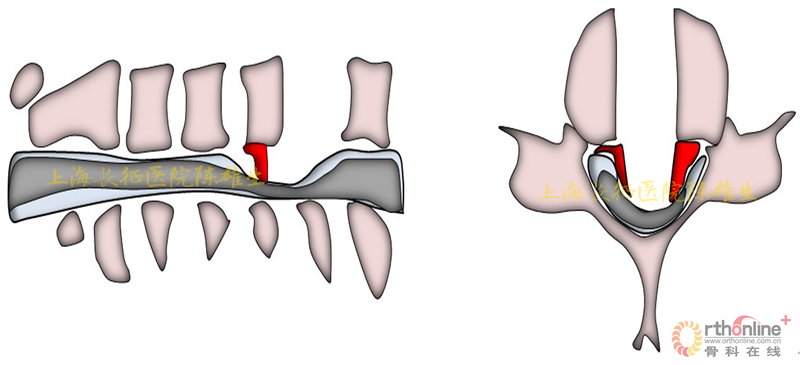

3.3.硬膜囊骨化的处理

临床实践发现,颈椎OPLL硬膜囊骨化物往往与OPLL骨化物融合,而与蛛网膜极少粘连。因此术中处理时,把持椎体后壁,将骨化物整体远离脊髓方向逐步抬起,直视下切除硬膜囊骨化物,尽量保留蛛网膜的完整性(图15)。缺损的硬膜囊的蛛网膜表面可用人工硬脊膜覆盖保护。

图15